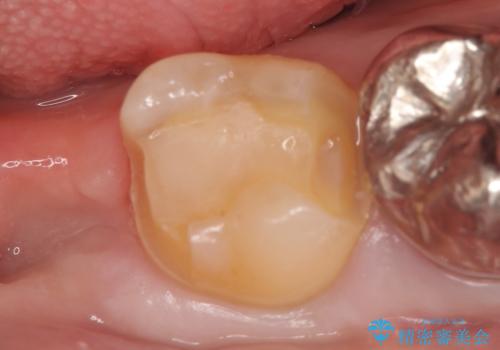

- 冷たいものを飲むと右下の奥歯が痛むので診て欲しいといらっしゃった方の症例です。

銀歯及び虫歯を除去後、より適合の良いPGA(ゴールド)インレーによる修復を行いました。

- PGA(ゴールド)インレー…¥60,000費用は治療当時の料金となります